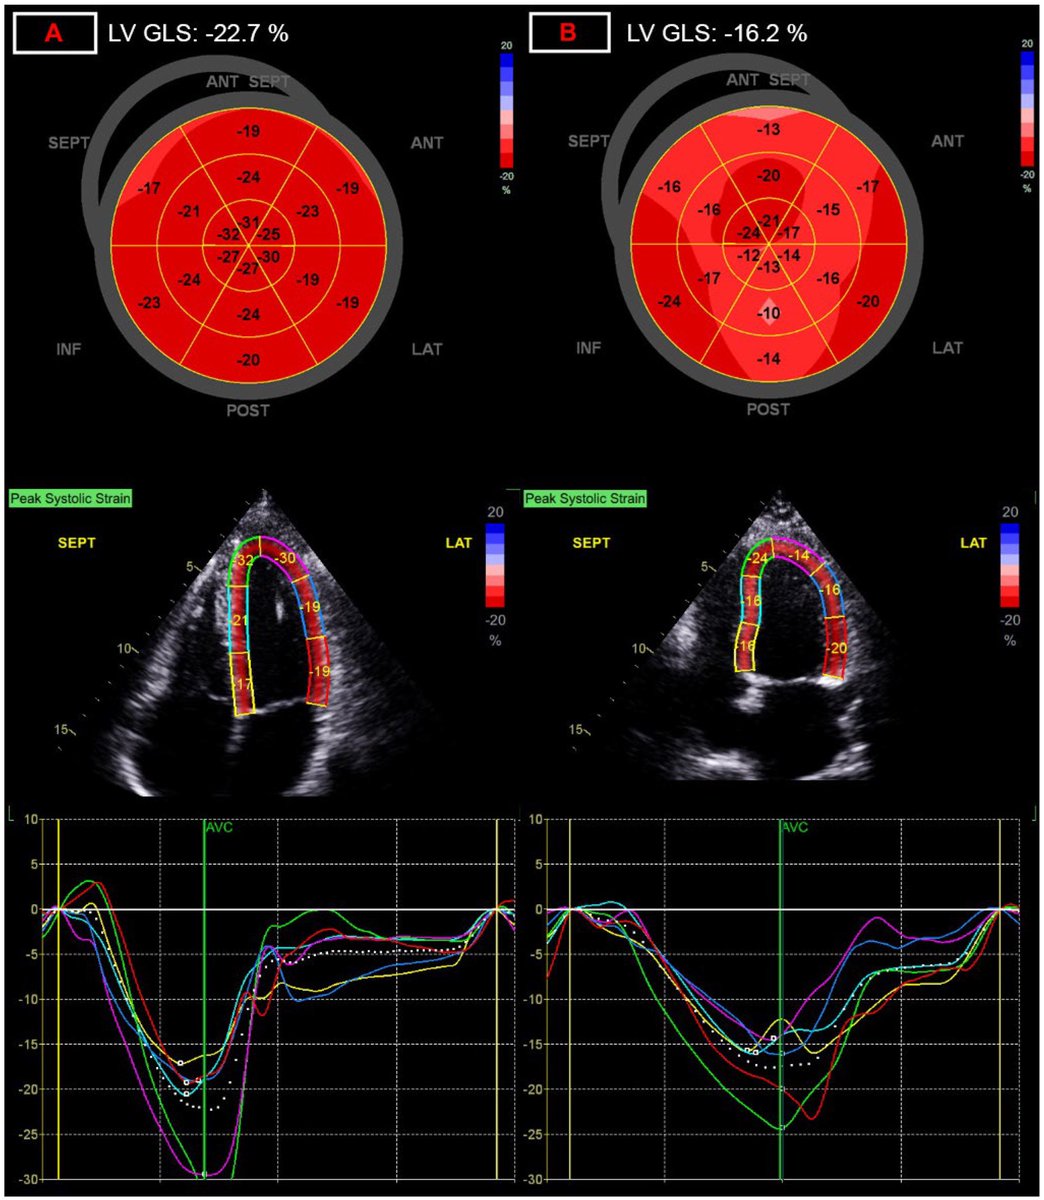

➡️ In a prospective case–control study, children with prior SARS-CoV-2 infection showed a persistent reduction in left ventricular global longitudinal strain (GLS) up to 1 year post-infection.

Despite normal conventional echocardiographic parameters, GLS was significantly reduced — indicating subclinical myocardial dysfunction that would otherwise be missed on routine echo. 1/Image

The reduction in GLS was most pronounced in children with moderate to severe acute COVID-19, suggesting a severity-dependent relationship between infection and post-infectious myocardial changes. 2/ Image